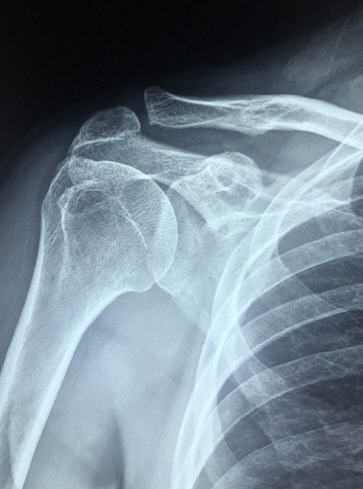

🧪 회전근개 파열 진단 방법

| 검사 방법 | 판단 내용 | 정확도 |

|---|---|---|

| X-ray | 뼈 및 석회화 상태 확인 | ★☆☆☆☆ |

| 초음파 | 실시간으로 힘줄 움직임 체크 | ★★★★☆ |

| MRI (가장 정확함) | 파열의 크기, 위치 및 심각도 확인 | ⭐⭐⭐⭐⭐ |

대부분의 경우 MRI 검사가 치료 방향을 결정하는 데 필수적입니다.